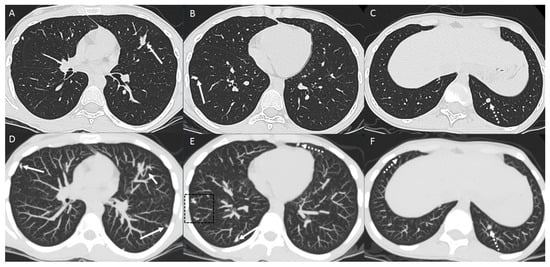

2.1. Parenchymal Metastasis

2.4. Lymphangitic Carcinomatosis